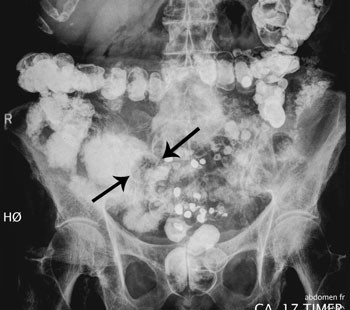

Gastroskopi viste normale funn i oesophagus, ventrikkel og duodenum. CT abdomen og bekken viste et sentralt midtlinjebrokk som inneholdt tynntarm. Det var flere små væskenivåer i tynntarmen og tykktarmen helt ned til endetarmen. Verken tynntarm eller tykktarm var utvidet. I tarmene, «mest sannsynlig i coecum», ble det beskrevet «et ovalt formet ca. 2,8 x 2 cm stort legeme» (fig 1). Dette inneholdt ikke kalk, og var kun synlig som en defekt i kontrasten. Det var ikke påvisbare ekspansive eller infiltrative prosesser. Det var ingen påvisbar irritasjon i buken og ikke fri væske. Noen dager senere viste ny røntgen tarmpassasje lett til moderat utvidede tynntarmer fylt med kontrast 3 timer etter kontrasttilførsel. Først etter 17 timer hadde kontrasten passert over i en normalt vid tykktarm og rectum. Utvidelsen i proksimale tynntarm var da gått tilbake, og tynntarmen var gassfylt bare i lett grad.

CT var hos vår pasient ikke diagnostisk. Det var ikke luft i galleveiene, og gallesteinen inneholdt ikke kalk. Dermed var den kun synlig på CT som en defekt i kontrasten. Det var ikke mulig å si hva denne representerte, og lokaliseringen ble feilaktig antatt å være i coecum. Ved ettergransking er steinen også synlig som en kontrastdefekt i tynntarmen på passasjebildene (fig 2). Både CT og den første kontrastundersøkelsen av passasjen underestimerte utvidelsen av tynntarmen.